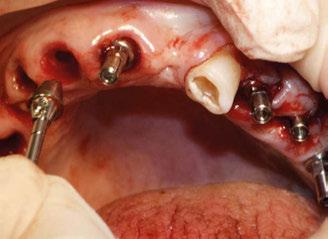

Figura 3. Visión intraoral oclusal mandibular. Figura 4. Visión intraoral frontal. Figura 1. Visión intraoral oclusal maxilar. Figura 2. Visión lateral izquierda intraoral. Figura 7. Escaneado intraoral maxilar con Dexis IS3700. Figura 8. Escaneado intraoral mandibular con Dexis IS3700. Figura 5. Visión extraoral lateral sonrisa.

Ejecución técnica quirúrgica mediante férula guiada Bajo anestesia infiltrativa realizamos extracciones atraumáticas de todas las piezas a excepción de los dientes que actúan como anclaje o pilares para la fijación de la férula quirúrgica (Figuras 20 y 21). Seguidamente insertamos la férula comprobando una buena adaptabilidad y estabilidad

(Figuras 22 y 23). Se realiza fresado transgingival mínimamente invasivo y guiado hasta la inserción de los implantes, siguiendo el protocolo preestablecido e indicado (Figuras 24 a 26).

Durante la colocación de los implantes comprobamos una inserción con torque superior a 35 N/cm2

Retiramos la férula y comprobamos una correcta estabilidad primaria mediante mediación de valores

ISQ favorables en la mayoría de los implantes. Seguidamente se extraen los dientes remanentes que han actuado de medio retentivo para la férula quirúrgica.

Dentro de la fase quirúrgica propiamente dicha, una vez terminada la inserción de los implantes y

comprobada su estabilidad primaria, colocamos pilares transepiteliales

Multiplus para registrar una impresión digital mediante escaneado sobre ellos (Figuras 27 a 29)